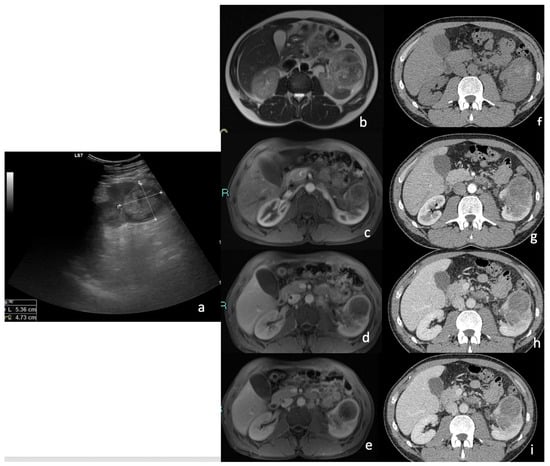

3.2. Contrast-Enhanced Ultrasound (CEUS)

| CEUS Features | % | n. | p > 0.05 |

| 70.3% | 19 | p < 0.05 |

| 29.7% | 8 | p > 0.05 |

| 0% | 0 | p > 0.05 |

| 52.2% | 12 | p < 0.05 |

| 29.6% | 8 | p > 0.05 |

| 25.9% | 7 | p > 0.05 |

| 62.9% | 17 | p > 0.05 |

| 37.0% | 10 | p > 0.05 |

| 81.5% | 22 | p < 0.05 |

| 11.1% | 3 | p > 0.05 |

| 7.4% | 2 | p > 0.05 |